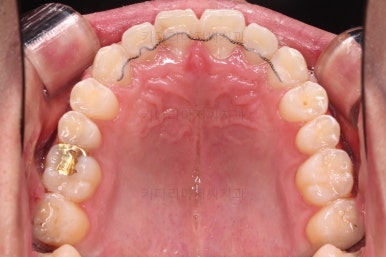

초진 시 입안의 모습입니다.

비교적 고른 편이긴 하나 아랫니가 전반적으로 밀려 나오면서 앞니끼리 부딪혀 있는 양상이고요.

어금니 맞물림도 긴밀하게 톱니바퀴처럼 위아래가 맞물려 있는게 아니라 엉성한 모습이죠.

앵글씨 3급 부정교합이라고 하는데요.